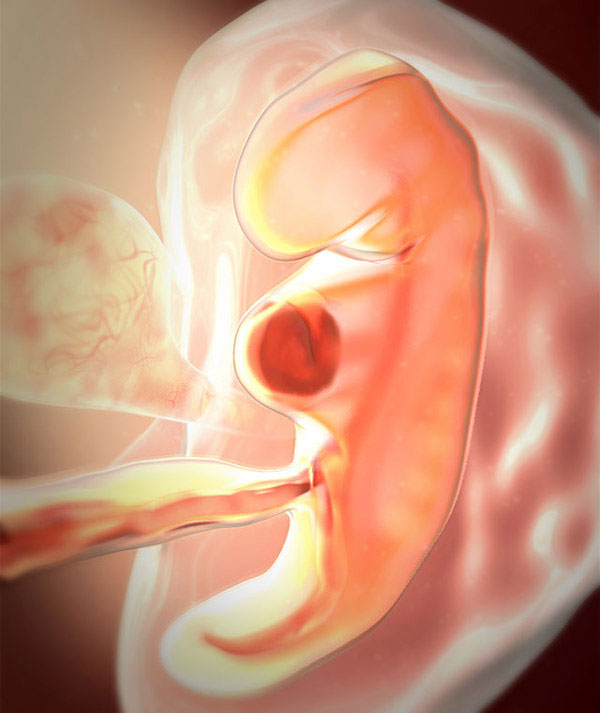

baby_week_5

rozwój płodu w 5 tygodniu ciąży

Jeśli wiek ciążowy wynosi 5 tygodni, mówimy o zarodku. Przeszedł już przez kilka etapów swojego rozwoju:

Szybki podział komórek trwa. Do końca piątego tygodnia rozmiar przyszłego płodu może osiągnąć 1,5 mm, a jego waga wyniesie około 1 g.

Jajo płodowe zawiera w sobie prawdziwy cud. To maleńkie ciało, na którym guzki są już widoczne w miejscu głowy, kończyn, a nawet palców. W miejscu uszu pojawiają się doły, obserwuje się przerwę w jamie ustnej, a także oczy. Teraz tworzenie i rozwój naczyń krwionośnych trwa w pełnym toku. Przyszłe dziecko ma już własną grupę krwi!

Ponieważ w zeszłym tygodniu dziecko było już „zdeterminowane” seksem, w piątym tygodniu położniczym układa się specjalne komórki zarodkowe - przyszłe plemniki i jaja. Co jeszcze powstaje w zarodku?

• Skóra gęstnieje i staje się dwuwarstwowa.

• Drogi oddechowe i przewód pokarmowy są oddzielone.

• Zaczyna się tworzenie tarczycy.

• Rurka nerwowa przygotowuje się do przekształcenia w tkankę kręgosłupa i rdzenia kręgowego.

• „Rozpoczyna” tworzenie się układu moczowego i jelitowego.

Kolejny ważny proces rozpoczyna się w piątym tygodniu: tworzenie się łożyska. Przez miejsce dziecka i pępowinę nienarodzone dziecko będzie otrzymywać składniki odżywcze przez krew matki do porodu i pozbyć się produktów rozpadu.

Pod koniec piątego tygodnia serce przyszłego dziecka zaczyna bić. Na początku jego ciosy są nierównomierne, jakby sprawdzały siłę. Ale bardzo szybko ten malutki narząd będzie działał z pełną siłą.